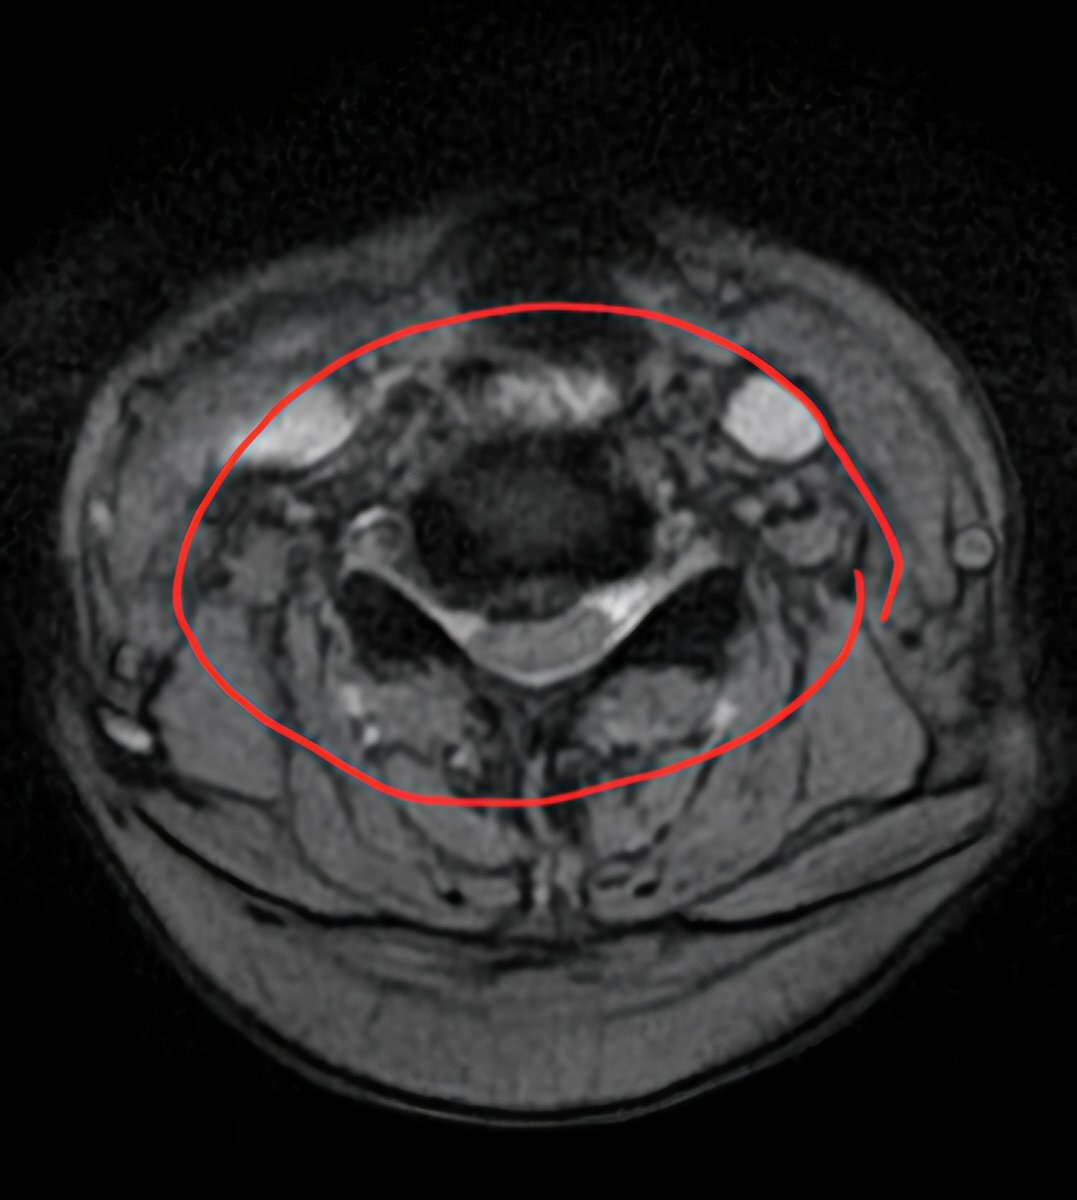

昨日診断された頸椎ヘルニアのMRI画像。縦に輪切りにされた5~6番目がずれてます。他2枚は横に輪切りにした画像。一枚は正常な頸椎で楕円になってますが、もう一枚はかなり潰された頸椎。ここが患部。なんか見てるだけで怖い。#頸椎ヘルニア #頚椎ヘルニア #椎間板ヘルニア pic.x.com/EpQGHwUqeI